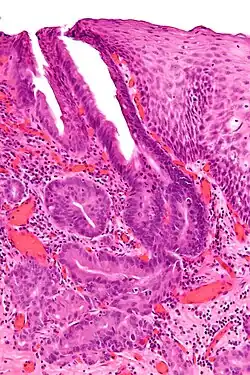

Unter normalen Umständen ist die Speiseröhre durchgängig mit Plattenepithel ausgekleidet, das eine hohe mechanische Belastbarkeit garantiert. Es ist allerdings gegen den Einfluss von Magensäure wenig widerstandsfähig. Unter dem Einfluss einer länger bestehenden Reflux-Erkrankung, also dem unphysiologischen Rückfluss von Magensäure in die Speiseröhre, das sich in Sodbrennen äußert, wird das Plattenepithel zu magenähnlichem Epithel umgewandelt. Diese Umwandlung wird Barrett-Metaplasie genannt. Es entstehen umschriebene Bereiche adenoiden Epithels, die mit einer geringen Wahrscheinlichkeit entarten.